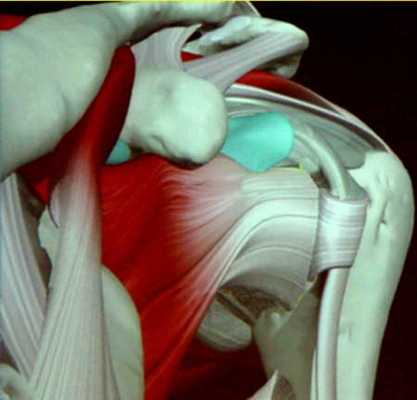

Патологии плечевого сустава в большинстве случаев являются следствием особенностей его анатомии. Большой объём движений в плечевом суставе обеспечен за счёт малой площади покрытия головки плеча суставной поверхностью гленоидальной впадины (см. рисунок). Стабильность обеспечивается за счёт капсульно-связочного аппарата.

На следующем рисунке показано как выглядит суставная губа на срезе, это хрящевой ободок, который:

- Несколько увеличивает площадь покрытия впадиной головки; Является местом прикрепления плече-лопаточных связок (спереди их 3: переднее-верхняя, средняя и нижняя).

Основными мягкоткаными стабилизирующими структурами являются:

- Хрящевая губа с прикреплёнными к ней плече-лопаточными связками (спереди - верхняя, средняя и нижняя); Компоненты вращающей манжеты плеча: подлопаточная, надостная, подостная, большая и малая круглые мышцы.